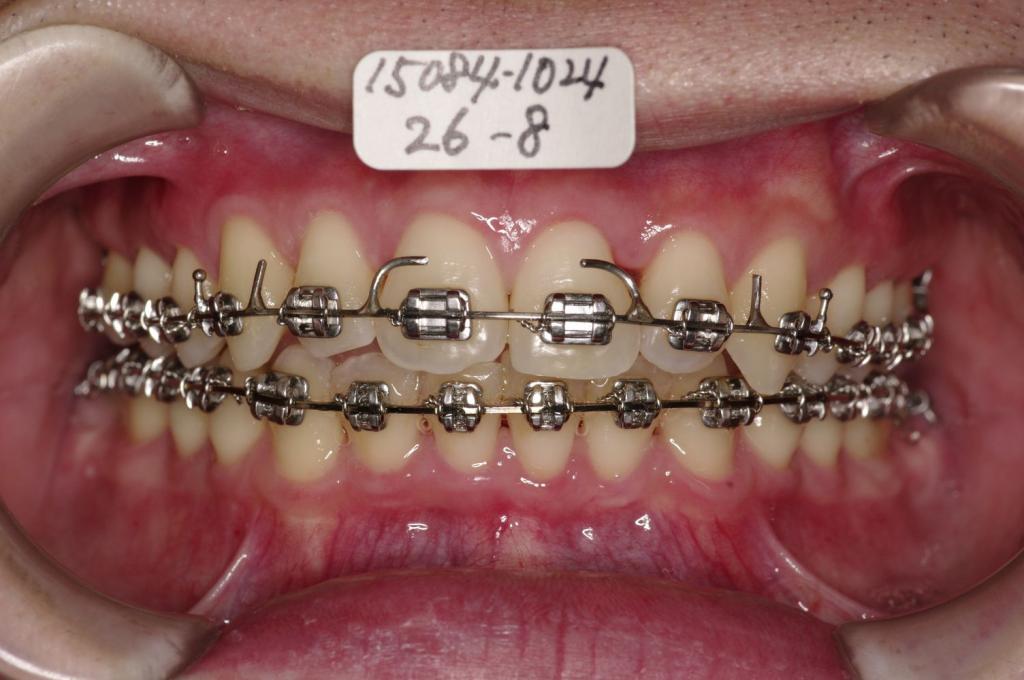

装置の種類及び治療法 診断:上顎前突 過蓋咬合

治療方法および装置:マルチブラケット装置

High pull J-hook headgear

抜歯:非抜歯

装置写真

治療前

歯並び・咬み合わせ・八重歯・乱杭歯の矯正治療前口内写真NO.1201